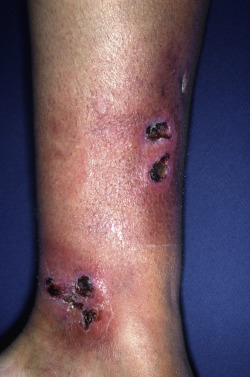

Erythema induratum favors the calves, and ulceration is frequent. Oily fluid often drains from the ulcers. Pancreatic panniculitis presents as indurated plaques, most commonly on the lower legs. The subcutaneous fat elsewhere may also be affected, and multiple areas may be affected. Tenderness of the ankles is commonly reported. Another form of panniculitis is subcutaneous fat necrosis of the newborn, which also presents as hard, indurated areas and demonstrates characteristic intracellular crystalline rosettes histologically.

Lipodermatosclerosis represents ischemic fat necrosis associated with venous stasis. Early lesions present as tender nodules of the lower leg. Over time, the skin becomes erythematous and indurated, with constriction of the lower leg giving the appearance of an inverted champagne bottle. Factitial and infectious panniculitis range in appearance from erythematous nodules to draining indurated plaques, whereas lipodystrophies present with loss of subcutaneous fat, giving a gaunt and muscular appearance. This section of the atlas will focus on the range of cutaneous findings that accompany diseases of the fat.